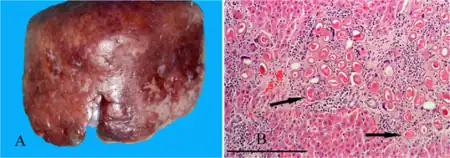

| a,b)Hepatic capillariasis | |

- Hepatic capillariasis, caused by Capillaria hepatica[4]